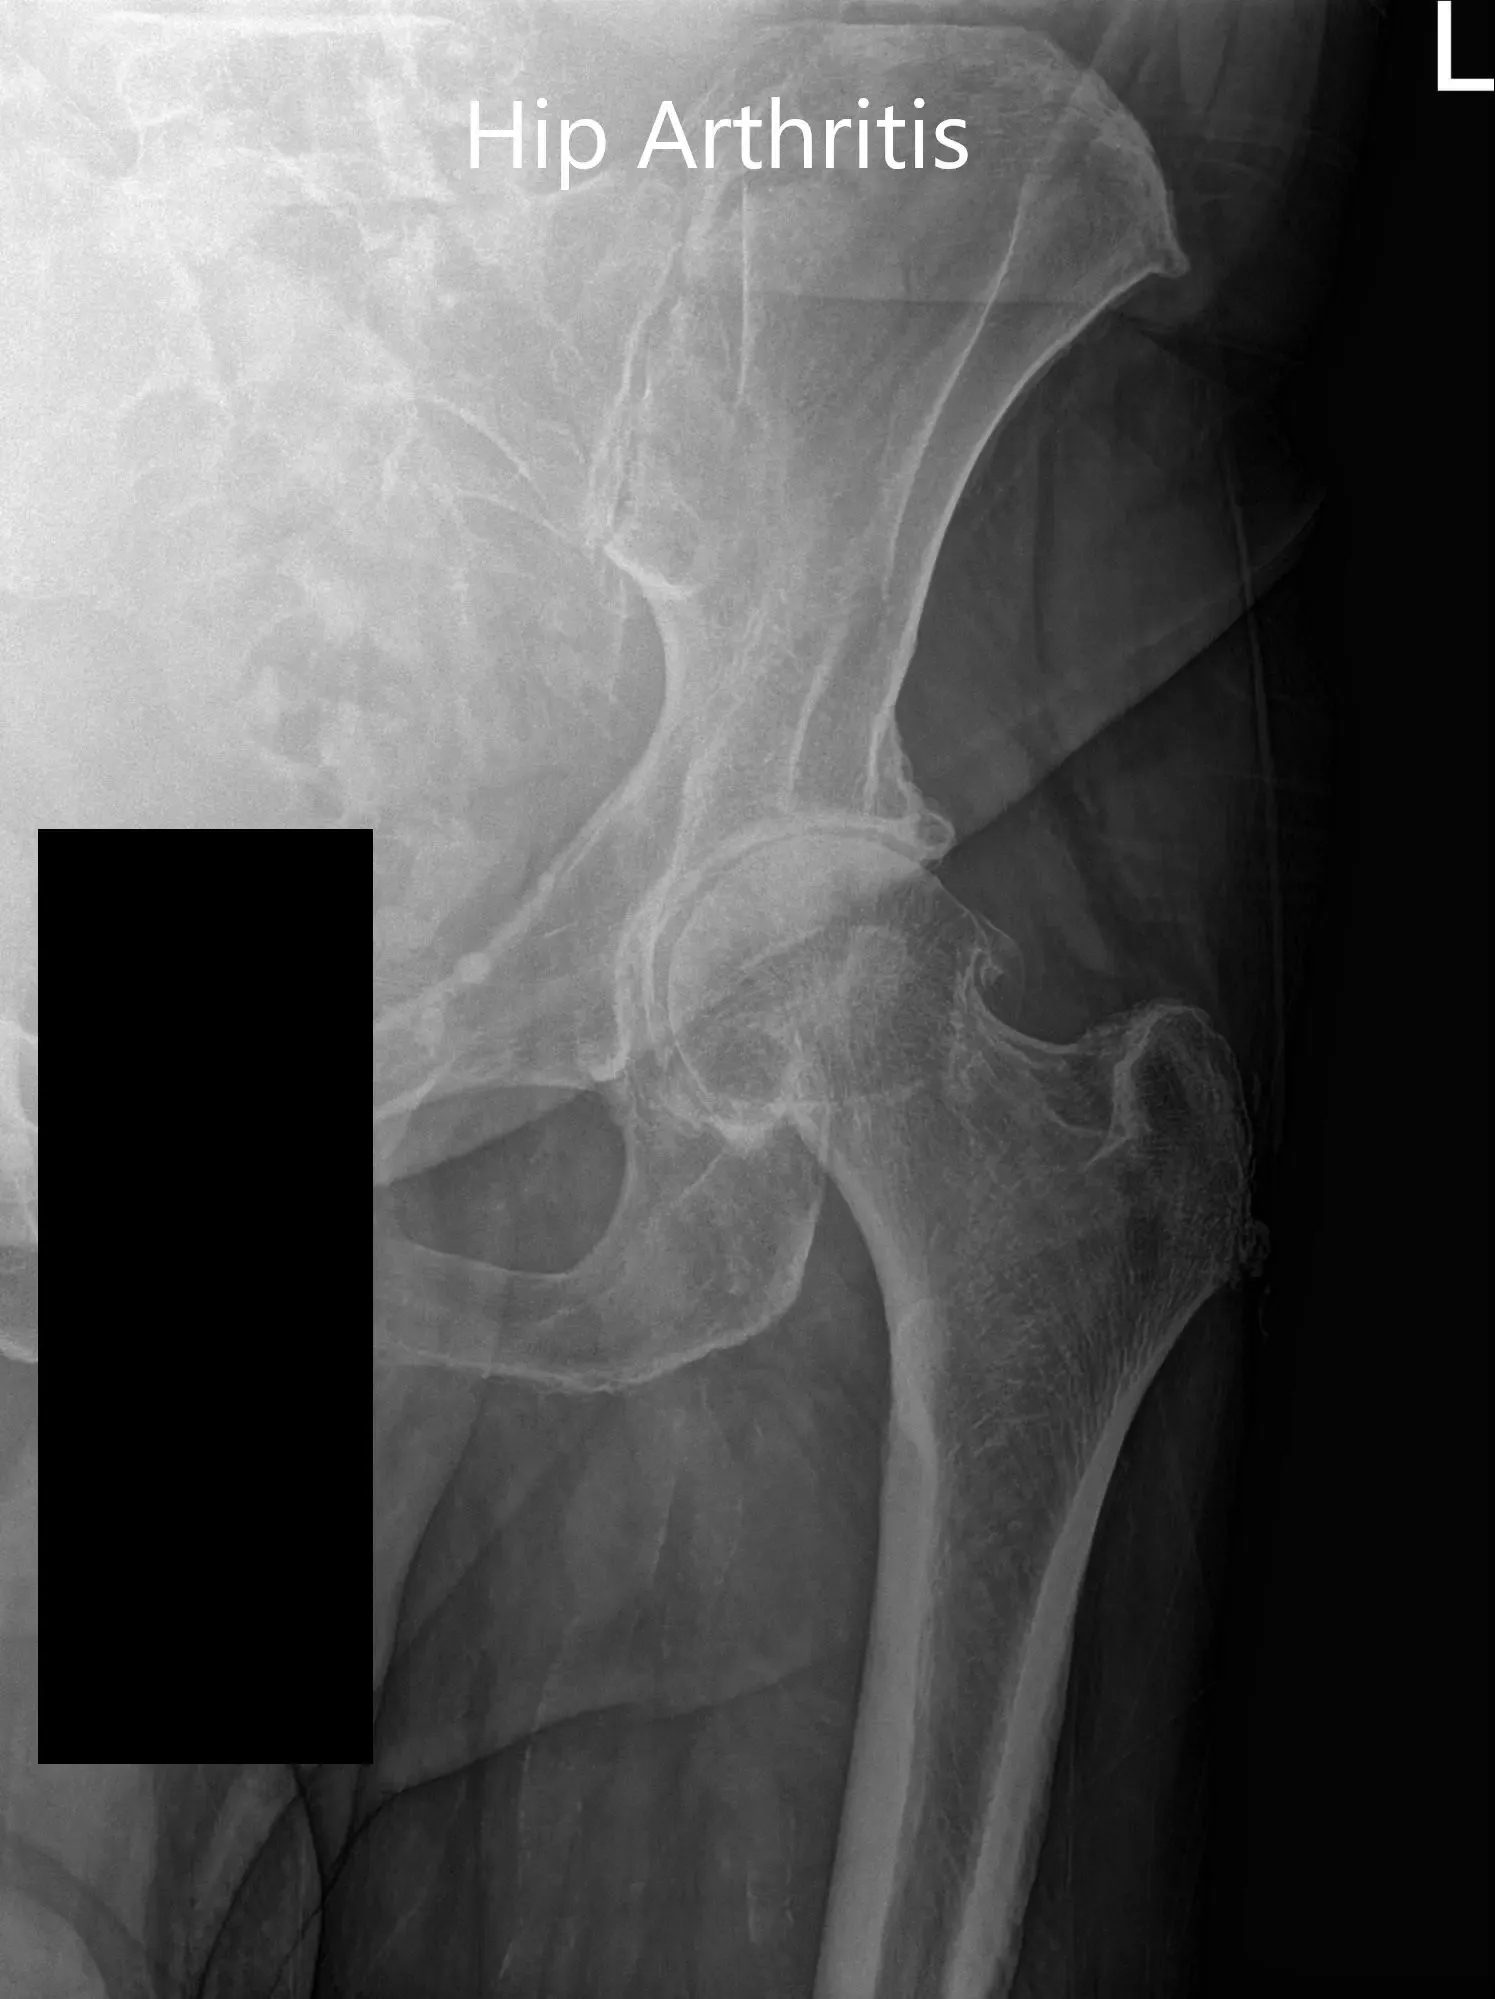

Las imágenes revelaron una osteoartritis severa en la cadera izquierda. Teniendo en cuenta las condiciones médicas de los pacientes y el dolor de cadera que limitan el estilo de vida, se le recomendó una prótesis total de cadera para la izquierda. Se discutieron extensamente los riesgos, beneficios y alternativas. Ella aceptó seguir adelante con el procedimiento.

Radiografía preoperatoria de la cadera izquierda que muestra visión AP y vista lateral con patas de rana